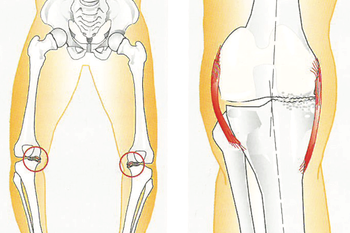

Dei nedslitte leddflatene skaper kraftig irritasjon i leddet. Dette fører til smerte og hevelse. Hevelsen skuldast at det irriterte kneleddet danner meir leddvæske enn normalt. Etter kvart som artrosen auker, kan sjølve leddet forandra seg. Det dannar seg beinpåleiringar og forkalkningar, ein kan bli hjulbeint eller kalvbeint. Slitasjen må ikkje nødvendigvis omfatta heile kneet. Ofte vil berre delar av leddet utvikla slike forandringar.